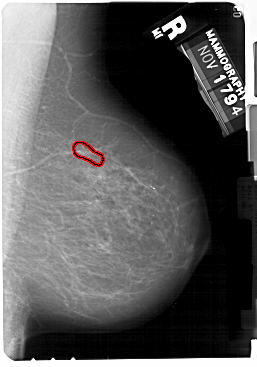

A_1175_1.RIGHT_MLO

RIGHT_MLO LINES 5491 PIXELS_PER_LINE 3841 BITS_PER_PIXEL 12 RESOLUTION 43.5 OVERLAY

FILE: A_1175_1.RIGHT_MLO.OVERLAY

TOTAL_ABNORMALITIES 1

ABNORMALITY 1

LESION_TYPE CALCIFICATION TYPE PLEOMORPHIC DISTRIBUTION LINEAR

ASSESSMENT 4

SUBTLETY 3

PATHOLOGY MALIGNANT

TOTAL_OUTLINES 1

BOUNDARY